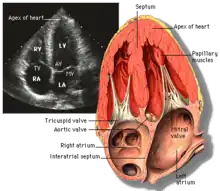

Axes

The images obtained with echocardiography are in reference to the heart itself. Two key axes of the heart are the long axis and short axis. The long axis is an imaginary line from the apex of the heart through the center of the tricuspid/mitral valve (depending on ventricle of reference). The short axis is perpendicular to the long axis and shows the heart in cross section. Axes are also defined for each valve with long-axis defined as that of blood flow, and short-axis is the plane perpendicular to the flow.

Apical four chamber (A4C)

This view is obtained at the apex of the heart and looking toward the base of the heart (where the valves are). In this view, the mitral valve, tricuspid valve, and all four chambers are visible. This view shows the right ventricle from base to apex and is a useful view to estimate RV systolic function. TAPSE (= tricuspid annular plane systolic excursion) is also measured in this view with M-mode through the lateral tricuspid annulus.